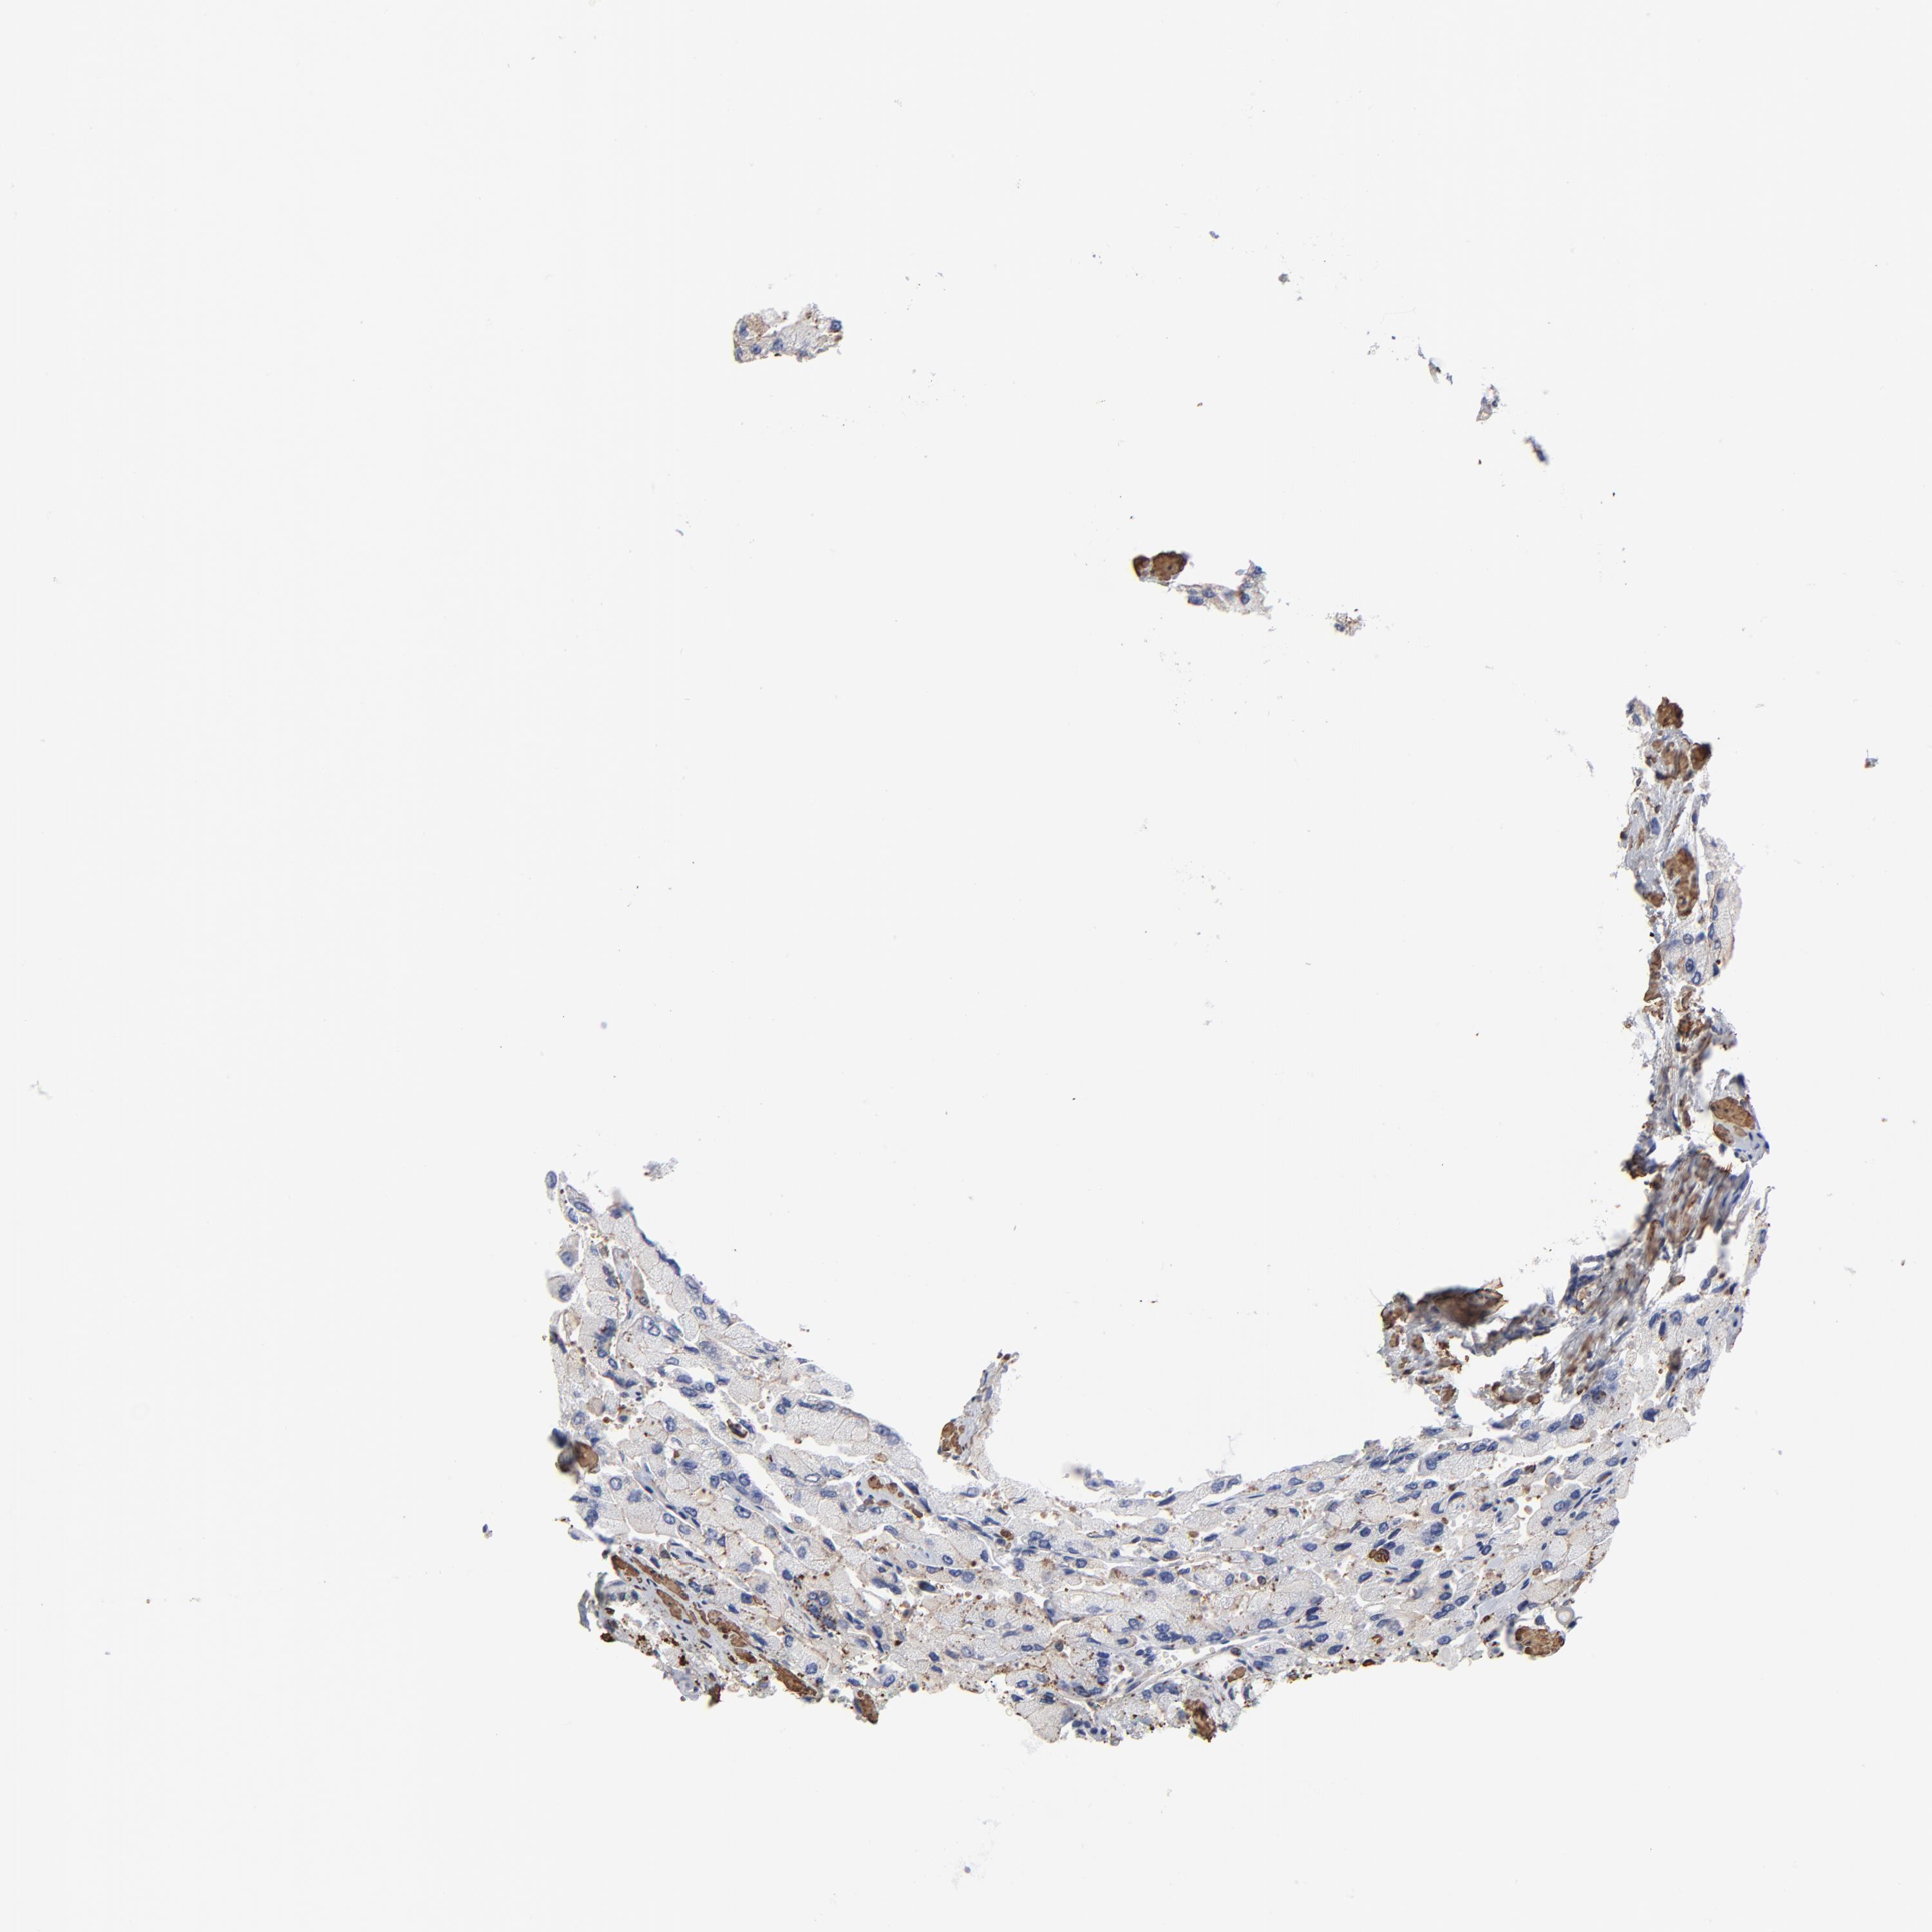

PROSTATE CANCER - Protein expressioni

A mouse-over function shows sample information and annotation data. Click on an image to view it in a full screen mode. Samples can be filtered based on level of antibody staining by selecting one or several of the following categories: high, medium, low and not detected. The assay and annotation is described here.

Note that samples used for immunohistochemistry by the Human Protein Atlas do not correspond to samples in the TCGA dataset.

Antibody stainingi

Antibody staining in the annotated cell types in the current human tissue is reported as not detected, low, medium, or high, based on conventional immunohistochemistry profiling in selected tissues. This score is based on the combination of the staining intensity and fraction of stained cells.

Each image is clickable and will lead to virtual microscopy that enables deeper exploration of all samples and also displays staining intensity scores, fraction scores and subcellular localization as well as patient and tissue information for each sample.

Adenocarcinoma, NOS

Adenocarcinoma, High grade

Adenocarcinoma, Low grade

Adenocarcinoma, Medium grade